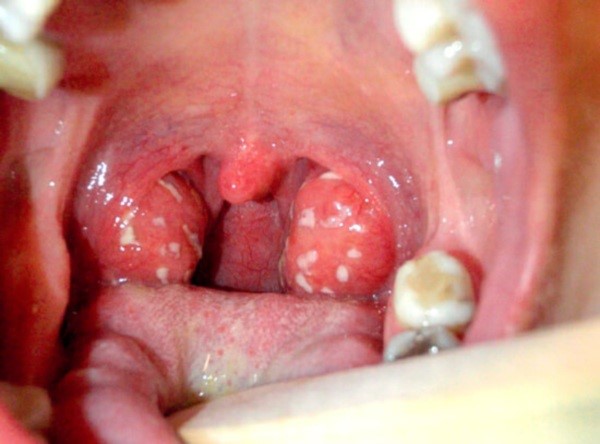

Фолликулярная ангина

Белые волдыри в горле: что это? Может быть фолликулярная ангина. Это тяжелое инфекционное заболевания, связанное с воспалением миндалин .

Болезнь является следствием переохлаждения у людей со слабым иммунитетом.

Вот почему страдают лимфатические узлы горла, расположенные на миндалинах.

Фолликулы – плотные сгустки лимфатической ткани – воспаляются и становятся похожи на белые узелки. Размер их обычно не превышает величину спичечной головки. На конце такого узелка может образоваться гнойник.

Сначала фолликулярная ангина может напоминать кишечную инфекцию. Но достаточно широко открыть рот и посмотреть в зеркало, чтобы убедиться в ошибочности диагноза: белые волдыри на миндалинах можно увидеть невооруженным глазом.

На стенке горла волдыри: фото фолликул при фолликулярной ангине.